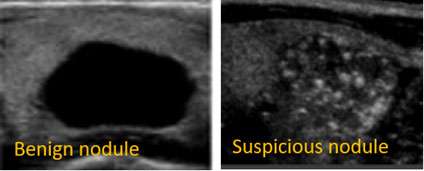

Not all thyroid nodules need a biopsy. For many thyroid nodules we see in our office, we choose not to biopsy because the ultrasound appearance is so reassuring. That is one way to avoid over treatment. For example, nodules that appear completely black on the inside (“anechoic”) are purely cystic, or filled with fluid. The chance of thyroid cancer for a cystic nodule is essentially zero and cystic nodules do not require biopsy. There are guidelines from the American Thyroid Association that will help your doctor determine which nodules to biopsy based on their size and how suspicious they look on the ultrasound.

There are certain factors that make a nodule suspicious for thyroid cancer. For example, nodules that do not have smooth borders or have little bright white spots (micro-calcifications) on the ultrasound would make your doctor suspicious that there is a thyroid cancer present. If the nodule appears suspicious on ultrasound and is larger than 1cm, the next step is to do a thyroid biopsy.